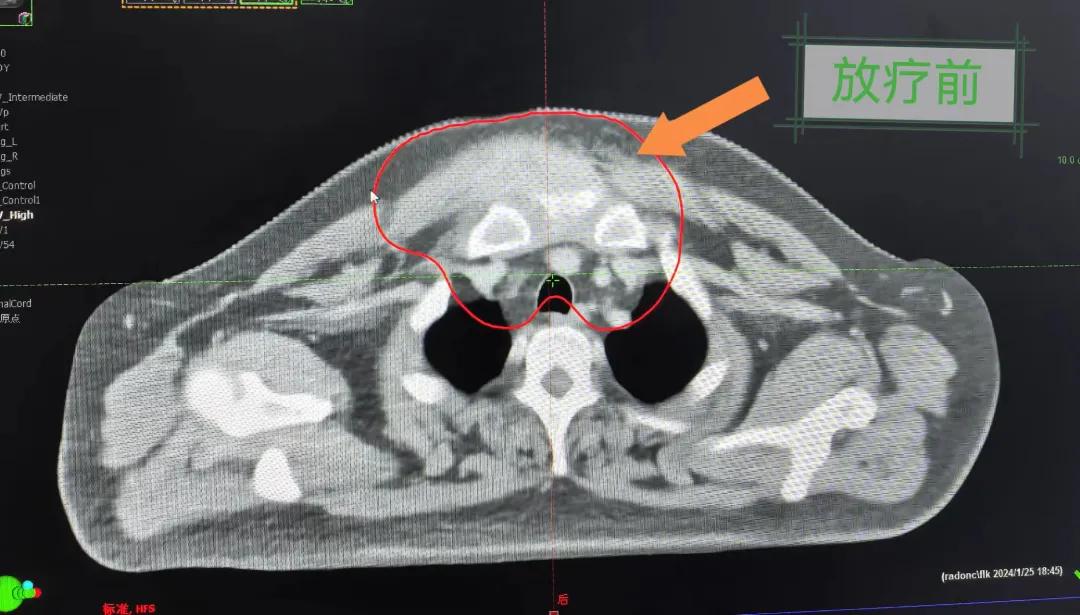

隨后,趙亮主任帶領(lǐng)放療團隊以最快的速度完成了患者的放射治療計劃,在保證放療精準打擊腫瘤的同時,利用先進的三維立體精確放療技術(shù),最大限度的避免心臟、肺部的損傷發(fā)生,整體治療精準度達到1mm以內(nèi)。經(jīng)過10次的放射治療后,患者疼痛已明顯減輕,胸部腫物肉眼可見的縮小,患者及家屬臉上終于露出久違的笑臉。

治療期間,患者沒有出現(xiàn)明顯不適,治療結(jié)束后,患者胸壁腫物由最初8cm縮小至約1cm,后患者至外科行手術(shù)治療。